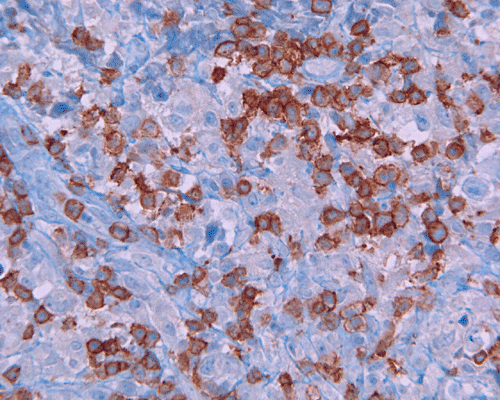

CD117

Paraffin sections: The entire volume of the tissue is made up of a granulomatous inflammation with poorly formed granuloma (Panel F, G, and H). The density of the lymphocytes is variable in different areas. In some areas, there is a rather intense lymphocytic infiltration accompanied by scant atypical cells with enlarged nulcei and prominent nucleoli (arrows in Panel I and J, Panel J is a higher magnification of Panel I). These atypical cells are quite easy to be missed. No microorganisms were identified by acid fast stain, PAS stain or GMS stain. The lymphocytes but not the atypical cells are positive for CD20 (Panel K) or CD3 (Panel L). The granulomatous background is strongly positive for CD68 (Panel M). Only rather faint positive staining for placental alkaline phosphatase (PLAP) is demonstrated and the interpretation is difficult as they are present in areas with crush artifact (Panel N). Many of the large, atypical cells are positive for CD117 (c-kit) (Panel O).

Immunohistochemically, the neoplastic cells show cytoplasmic membranous patten, sometimes diffuse cytoplasmic pattern, of staining for placental alkaline phosphatase (PLAP). Detection of c-kit (CD 117) in germinoma has been demonstrated and serves as a good diagnostic aid. Activating KIT mutations may contribute to tumorigenesis in germinoma 6, 7, 8. Syncytiotrophoblastic cells can be positive for human chorionic gonadotrophin (hCG). Occasional positive immunoreactivity for cytokeratin has been described and should not be taken as the sole evidence for embryonal carcinoma.